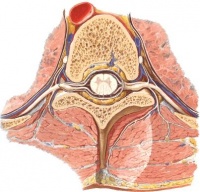

脑脊液的产生:在中枢神经系统内,脑脊液产生的速率为0.3ml/min,日分泌量在400-500ml。脑室内的脉络丛组织是产生脑脊液的主要结构。脉络丛主要分布在侧脑室的底部和第三、第四脑室的顶部,其结构是一簇毛细血管网,其上覆盖一层室管膜上皮,形似微绒毛。此微绒毛犹如单向开放的膜,只向脑室腔和蛛网膜下腔分泌脑脊液。也有人认为室管膜和脑实质也有产生脑脊液的作用。

脑脊液的流动具有一定的方向性。两个侧脑室脉络丛最丰富,产生的脑脊液最多,这些脑脊液经室间孔流入第三脑室,再经中脑导水管流入第四脑室。各脑室脉络丛产生的脑脊液都汇至第四脑室并经第四脑室的正中孔和外侧孔流入脑和脊髓的蛛网膜下腔。最后经矢状窦旁的蛛网膜颗粒将脑脊液回渗到上矢状窦,使脑脊液回流至静脉系统。脑脊液的回流(或吸收)主要取决于颅内静脉压和脑脊液的压力差以及血脑屏障间的有效胶体渗透压。脑和脊髓的血管、神经周围间隙和室管膜也参与脑脊液的吸收。